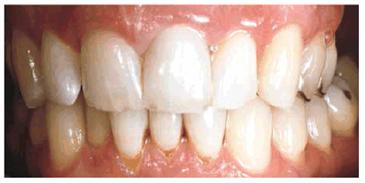

PROBLEM: A 56-year-old businessman presented with a desire to straighten

his anterior teeth. In addition, he was concerned about the wear and

irregularity of the incisal edges of his teeth (see Figures 24-4A 24-4B, and 24-4C). Orthodontics was presented as a

first option, but the patient declined this treatment option because of the

Figure 24-4A: Pretreatment-anterior view. Note the prominence of tooth #7 due to significant rotation and the slightly shortened appearance of tooth #10.

Figure 24-4B: Pretreatment-incisal view. Variations in available arch space for the lateral incisors are evident.

Figure 24-4C: Pretreatment-view of normal smile. Irregular incisal edges and incisal embrasures create an unbalanced esthetic appearance.